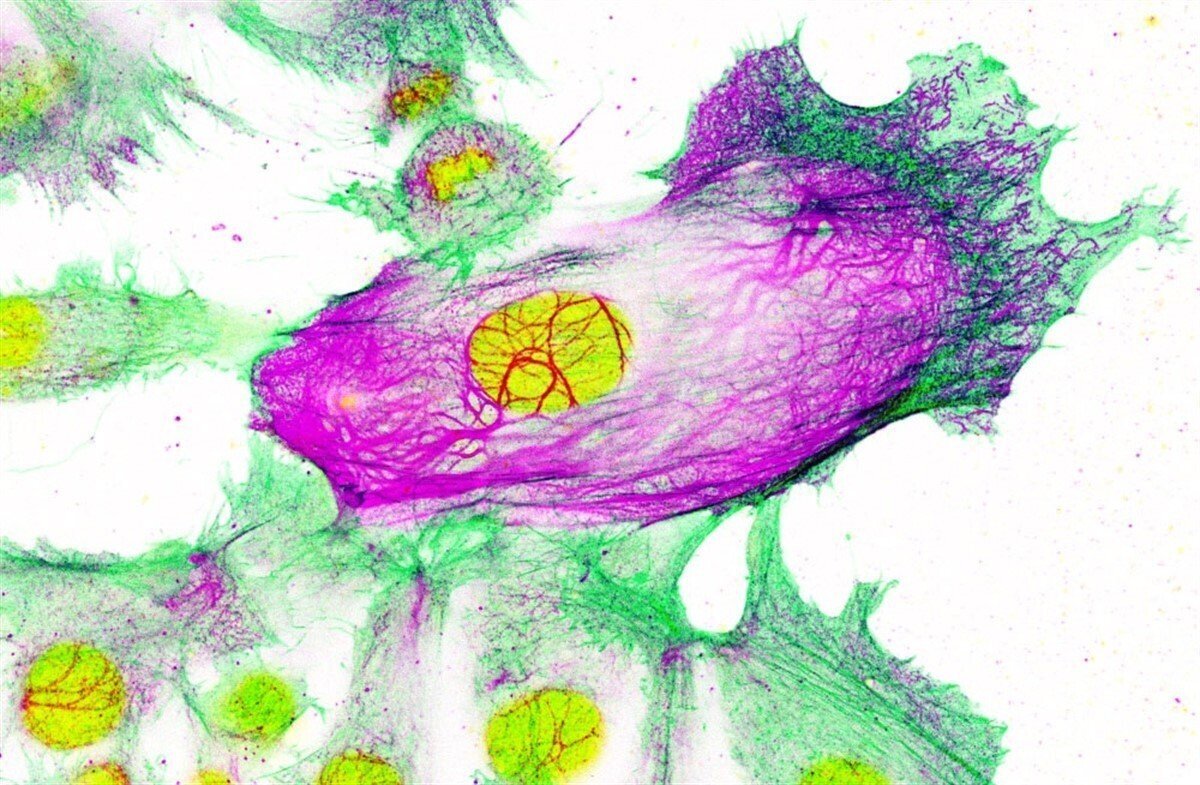

Mediante el estudio pormenorizado de los reordenamientos del ADN de estas células los investigadores identificaron una parte concreta que estaba muy alterada y que provocaba la amplia sobreexpresión de la keratina-80 (KRT80). Esta keratina es una proteína que forma parte de los filamentos intermedios (uno de los compontes principales del esqueleto celular que da forma y resistencia a las células).

Los investigadores descubrieron que en células resistentes KRT80 formaba una intrincada red de filamentos no observable en células no resistentes. La expresión de KRT80 en células resistentes estaba asociada con una mayor capacidad de estas células para cambiar de forma, invadir tejidos adyacentes de forma colectiva y metastatizar.